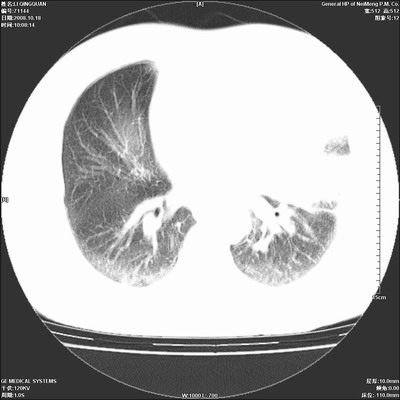

以下是引用duguo在2008-10-19 13:59:00的发言:[br]左肺上叶支气管狭窄,首先考虑中心型肺癌伴阻塞性肺炎\\肺不张.

以下是引用ybing在2008-10-19 12:58:00的发言:[br]左肺上叶阻塞性炎症-建议支气管镜进一步检查除外中央型肺癌

以下是引用随光逐影在2008-10-19 14:31:00的发言:[br]考虑左肺中央型肺癌并左肺上叶阻塞性肺炎,肺不张。